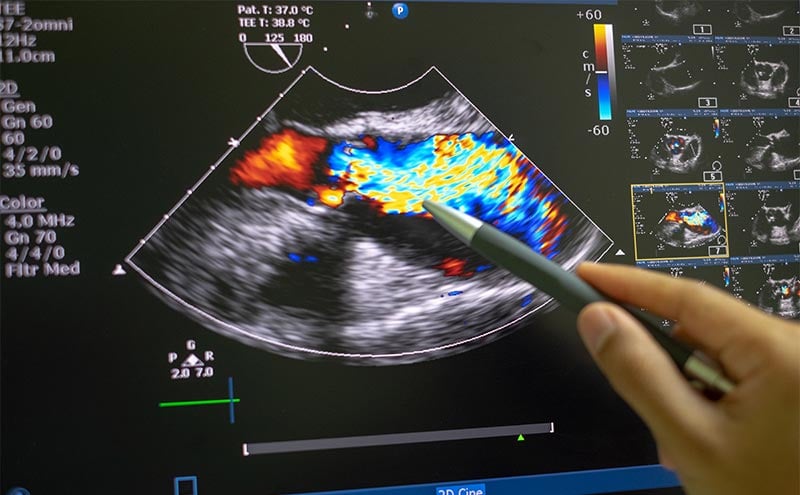

If the surface anatomy is not reliable in terms of probe placement, what can you do? Learn to recognize the bony anatomy by palpating the sternum and the ribs. This will give you a mental image of the intercostal spaces available for scanning. Think of these spaces as “windows” to send your ultrasound beams to the deeper cardiac structures. When first learning echo, get a sense of the superior and inferior heart borders by placing the probe on a high intercostal window (say, the second intercostal space) and scan inferiorly in each intercostal space. Note if there are A and/or B lines--which means the probe is over lung--as well any bone shadowing that would mean that the probe is over a rib. (Fig.5) Note intercostal windows that yield cardiac structures and that are relatively free of lung or rib artifact. There are usually 2-3 intercostal windows that meet this criteria for most patients. Find the intercostal window that gives the best definition of the myocardial walls. At this intercostal window, the insonation angle is perpendicular to the walls, giving the best image. Plant your palm or fingers to this intercostal window, because this is the best window for obtaining your parasternal long axis.